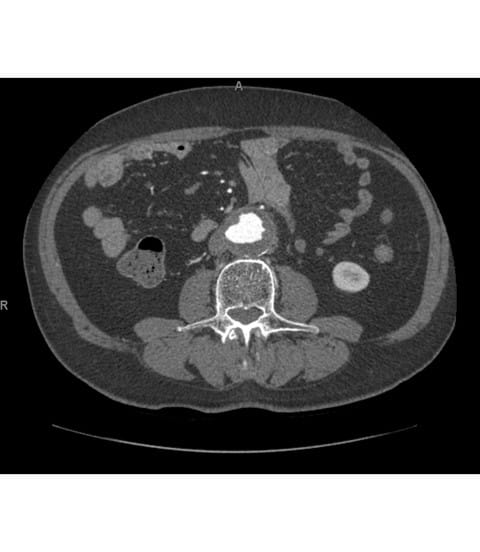

A 76-year-old male presented to UPMC for evaluation of aortoiliac aneurysm disease. His past medical history is also significant for mild emphysema, hyperlipidemia, lung and prostate cancer, and he has no family history of aneurysmal disease or connective tissue disorder. He is without symptoms of cardiac ischemia or peripheral claudication. His preoperative CT scan demonstrated the presence of a small infrarenal abdominal aortic aneurysm measuring 4.8cm, and bilateral large common iliac artery aneurysms, measuring 4cm and 3.8cm on the right and left, respectively. The internal iliac arteries were patent bilaterally (Figure 1 and 2). He underwent endovascular repair of his abdominal aortic aneurysm with placement of bilateral iliac branch endoprostheses (Gore Medical, Flagstaff AZ) for his bilateral common iliac artery aneurysms via percutaneous bilateral common femoral artery access (Figures 3-6). The patient tolerated the procedure well and was discharged on post-operative day two.

Figure 1: Infrarenal abdominal aortic aneurysm

Figure 2: Bilateral common iliac artery aneurysms